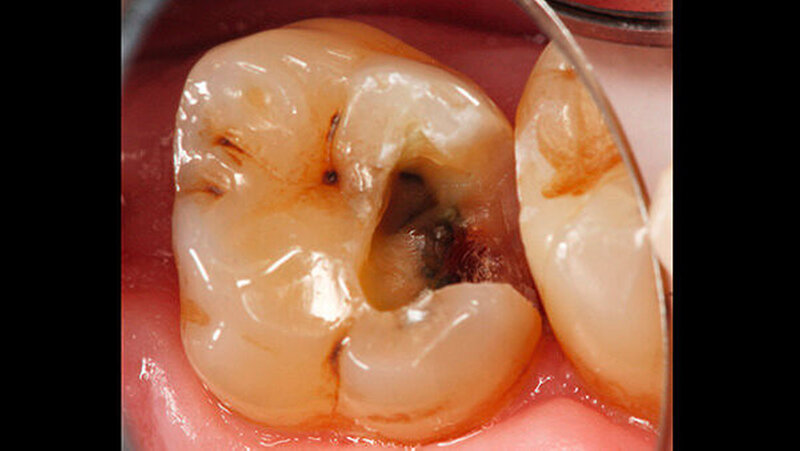

Bei der vollständigen Kariesentfernung kam es nicht zu einer Freilegung der Pulpa (Abbildung 3). Anschließend wurde eine Metallmatrize (HaweTofflemire Matrize, Kerr Dental) angelegt und verkeilt. Die Kavität wurde gereinigt und getrocknet.

Das Zementmaterial wurde nach Herstellerangaben angemischt und mittels eines kleinen Kugelstopfers (Dycal-Instrument) im Bereich der distalen pulpalen Wand appliziert und mit einem Heidemann-Spatel adaptiert. Das Material wurde damit gleichzeitig sowohl zur Caries-profunda-Behandlung als auch zur Unterfüllung eingesetzt. Nach einer Abbindezeit für das Material von zwölf Minuten wurde der Defekt mit einer Kompositfüllung restauriert (Abbildung 4).